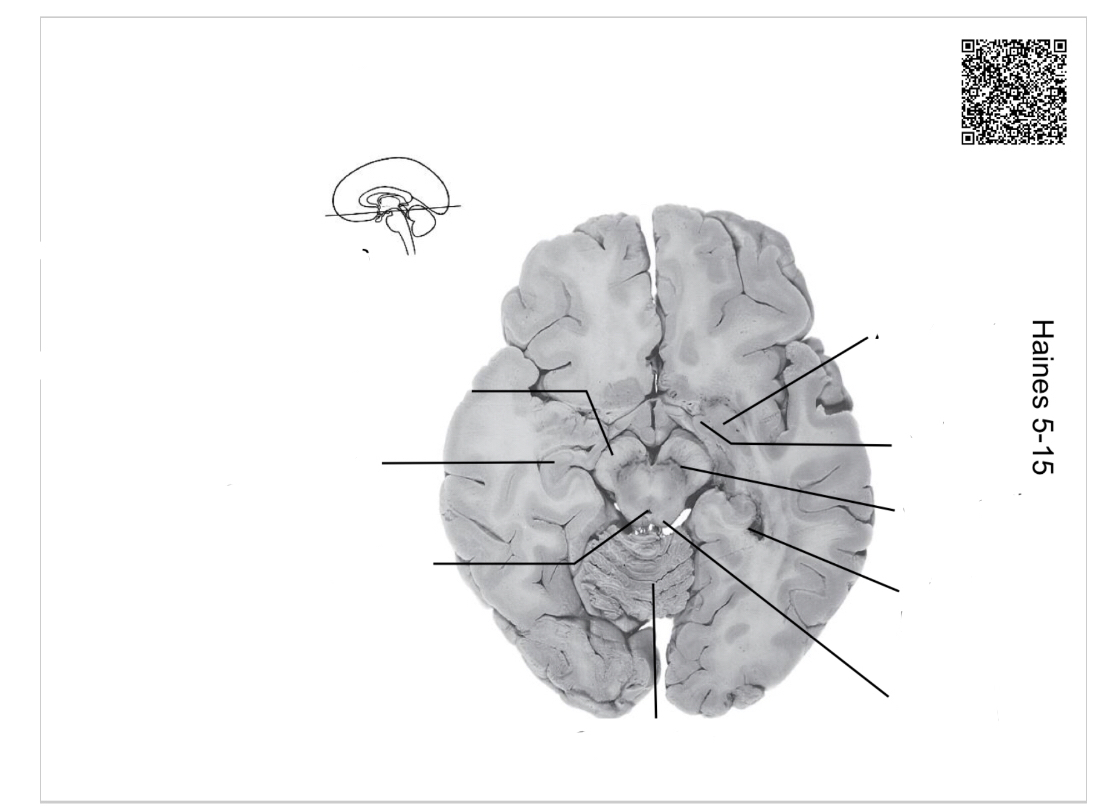

The structure indicated by the red line is?